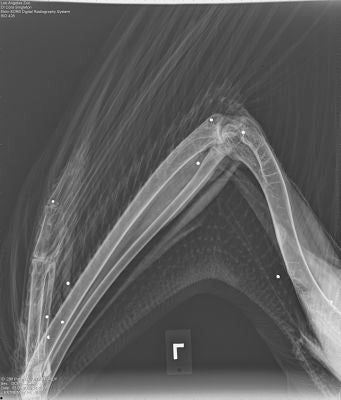

In early March, biologists with the Ventana Wildlife Society, based in Monterey, found the first critically endangered bird, an adult male riddled with lead shotgun pellets. Three weeks later they found a juvenile female condor in the same area with lead shotgun pellets in her wing and thigh.

As for the two wounded condors, they are recuperating at the Los Angeles Zoo. The male, #286, is in critical condition after being hit with 15 buckshot pellets (see photos below - courtesy Ventana Wildlife Society); his digestive system is debilitated due to lead poisoning and veterinarians must feed him through a tube. The second condor, #375, is in better condition, but the pellet injured her left wing and it’s unclear whether she will be able to fly; she was hit by a total of three pellets.